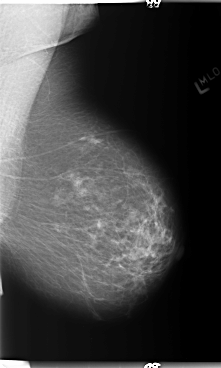

B_3362_1.LEFT_MLO

LEFT_MLO LINES 5888 PIXELS_PER_LINE 3528 BITS_PER_PIXEL 12 RESOLUTION 50 NON_OVERLAY